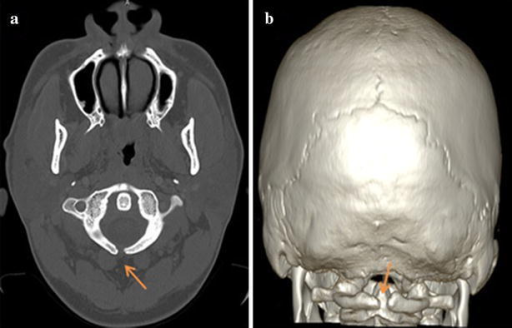

A meningocele may also form through dehiscences in the base of the skull. These may be classified by their localisation to occipital, frontoethmoidal, or nasal. Endonasal meningoceles lie at the roof of the nasal cavity and may be mistaken for a nasal polyp. They are treated surgically. Encephalomeningoceles are classified in the same way and also contain brain tissue.